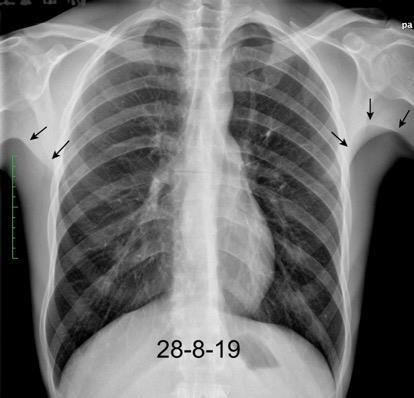

Asimetría de las partes blandas en Ca. de mama

Recidiva local Afectación de la piel